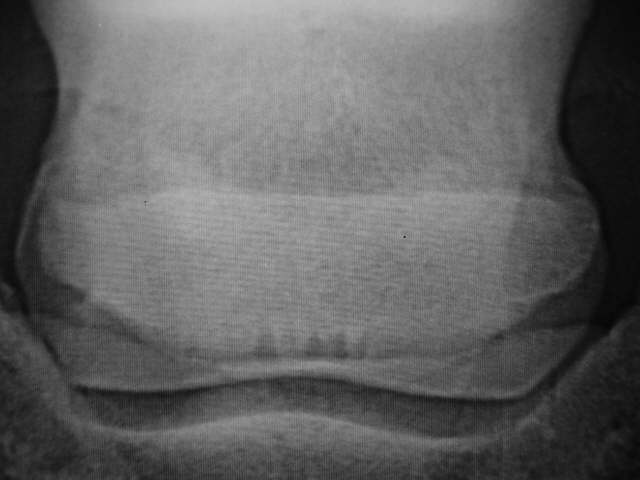

Krankh. Gefäßkanäle

Einige relativ kleine aber dicht zusammenliegende und teilweise konfluierende Gefäßkanäle. der untere Rand des Strahlbeines ist z. T. schlecht abgegrenzt, der linke Strahlbeinflügel scheint im Umbau zu sein. Röntgenklasse II - III